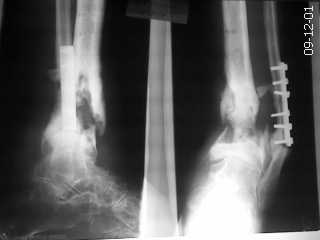

Поступил пациент с хроническим остеомиелитом. варусной установкой дистального отломка.

Пациент 35 лет. Оперирован по поводу перелома в ЦРБ. В дальнейшем нагноение-удаление пластины большеберцовой кости. В настоящее время имеется варусная установка голени, укорочение конечности. Имеется рана с гнойным отделяемым. Ходит с помощью костылей. Рассчитывать на серьёзные материалы для лечения смысла нет, т.к. больной неплатежеспособен.

Фото прилагаю. Коллеги, у кого какие есть соображения по лечению? Буду очень признателен.

Спасибо, за консультацию. Про ампутацию сам думал, но постеснялся озвучить. Сделали операцию-удалили очаг с секвестром, края отломков склерозированы, сделали остеоперфорацию, зачистили края и сопоставив по возможно большей площади фиксировали аппаратом. В итоге получилась ротация стопы кнаружи на 10 гр, укорочение конечности на 4 см.